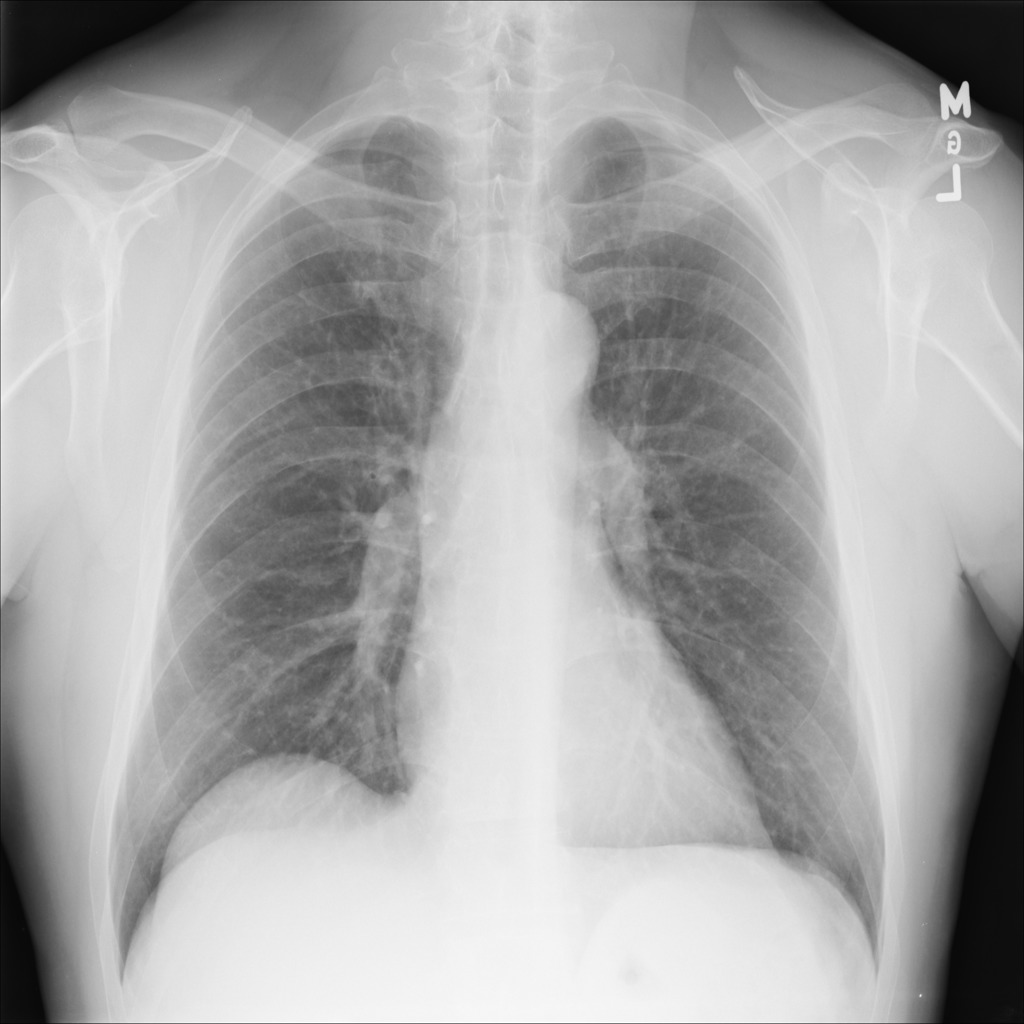

Examples of abnormal images generated by the proposed simulator are shown in the Figure 4.

Figure 4: Examples of abnormal images generated by the proposed simulator. The left is a normal lung image, and the middle is the abnormal image generated by the simulator. In the right, the location where the lesion has been inserted in the middle image is visualized by the blue bounding box.